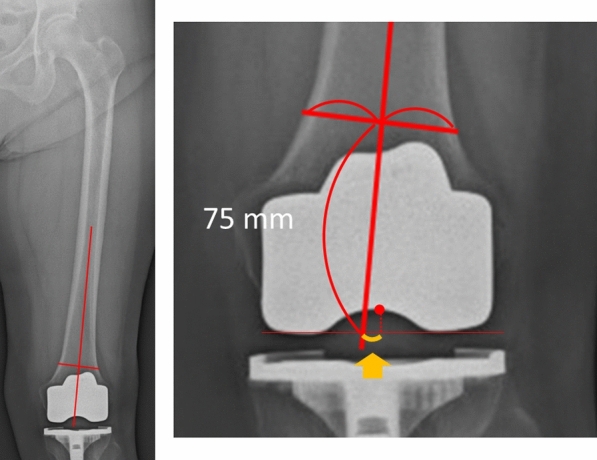

Methods: A total of 86 consecutive knees were included. The mediolateral positions of the femoral and tibial components were measured on the postoperative long-leg radiographs. The mediolateral position of the femoral and tibial components was defined relative to the femoral distal anatomical axis and the tibial mechanical axis. The lateral position of the component was denoted as positive. The lateral translation of the femoral and tibial components was defined as the distance between the preoperative femoral and tibial centers and the postoperative center of the respective component. The Knee Society Score (KSS), New Knee Society Score (2011 KSS), and the Timed Up and Go (TUG) test results were evaluated 2 years postoperatively. Spearman's correlation coefficient was calculated.